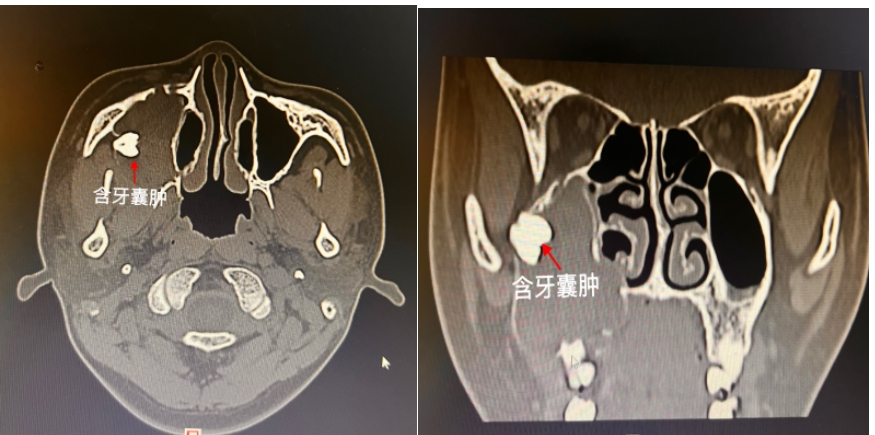

18岁的小强刚刚参加完高考,对未来的生活充满憧憬,可是最近三个月,右侧面颊部渐大的隆起让这个开朗的大男孩不禁开始了“颜值焦虑”。带着紧张的心情,家人陪同小强来到了湖南省第二人民医院(省脑科医院)耳鼻喉头颈外科就诊,门诊余丽亚副主任医师对患者进行了仔细的检查后,诊断为上颌窦含牙囊肿。(见图)

根据小强的检查结果(见图),右侧上颌窦已被囊肿及囊液填的满满当当,上颌窦原本坚实的骨质被囊肿压迫变薄甚至吸收。只剩下周围一层薄薄的皮质骨,在右侧上颌骨接近颧骨的位置,卡着一颗明晃晃的牙齿。综合分析后,余丽亚副主任医师建议患者尽快办理出院,行手术治疗。

上颌窦含牙囊肿一旦膨大,通常采用外科手术诊疗,术前完善CT等检查对明确肿物范围、位置及毗邻关系,对制定精准个体化手术诊疗方案相当重要。